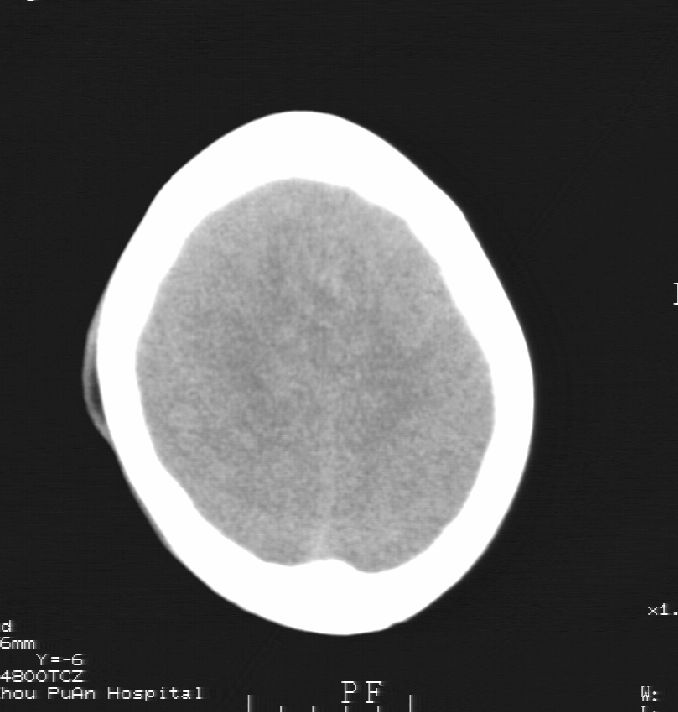

患者男,22岁,因外伤入院,低密度影ct值约-120hu。

脑水肿,头皮下血肿,胼胝体发育不全、合并脂肪瘤及钙化;建议必要时行mri检查。